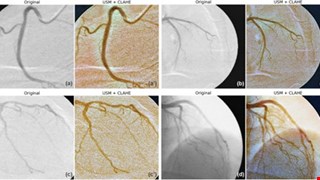

Optimizing ensemble U-Net architectures for robust coronary vessel segmentation in angiographic images

2025/3/16